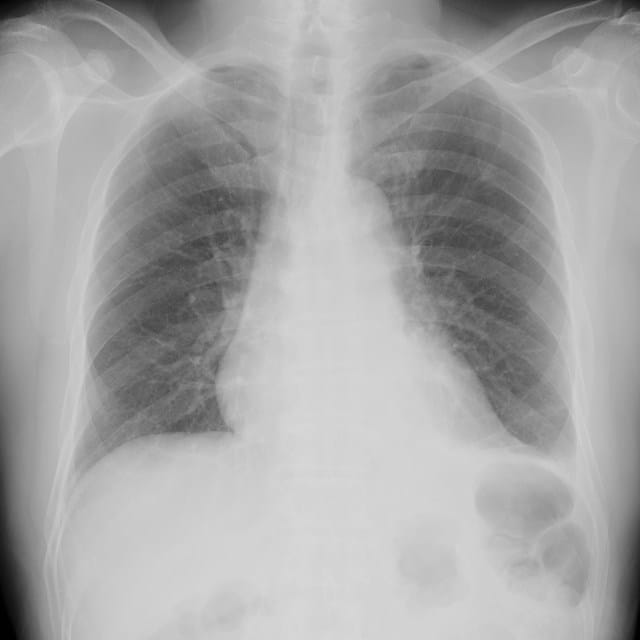

5. 늑막염 진단 과정과 검사 방법

늑막염 진단은 다음과 같은 과정을 통해 이루어집니다.

- 병력 조사 : 환자의 증상, 과거 병력 및 가족력을 상세히 파악합니다.

- 신체검사: 가슴 부위를 청진하여 이상징후를 확인합니다.

- 영상 검사 : 흉부 X선, CT 스캔 등을 통해 염증의 정도나 기타 이상을 평가합니다.

- 체액 검사 : 늑막액이 고여 있을 경우, 체액을 채취하여 분석합니다.